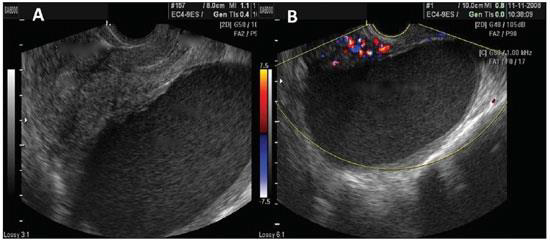

A endometriose é achado comum em mulheres inférteis e com dor pélvica, podendo se manifestar clinicamente de várias maneiras e com vários achados clínicos.

Paciente com quadro de infertilidade apresenta o seguiste achado ao ultrassom pélvico endovaginal (imagem anexa). Descrita como: "massa cística preenchida por ecos de baixa intensidade, de aspecto mais homogêneo que os cistos hemorrágicos e de parede bem delimitada. Sinal do "vidro moído". A massa foi abordada cirurgicamente, e quando se rompeu, saiu de sua cavidade uma substância similar à calda de chocolate. Trata-se provavelmente de um diagnóstico de: